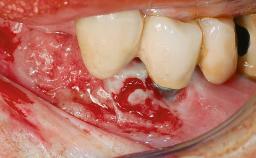

Le Fort I Interpositional Graft and Mandibular Sandwich Osteotomy for Maxillofacial Rehabilitation after Severe Periodontitis

A 47-year-old woman who had suffered from aggressive periodontitis requiring a number of periodontal interventions over more than 10 years was referred by her general dental practitioner and periodontologist for bone augmentation and implant therapy. Her failing dentition had already been scheduled for extraction. The patient expressed a desire for implant-supported fixed restorations and esthetic improvement of her lower face. She had agreed to consult with a maxillofacial surgeon after the referring dentist had suggested bone augmentation. An initial examination by the maxillofacial surgeon revealed mobility of all residual teeth in a patient who was very unhappy with the function of her removable partial dentures. Due to periodontally migrated flaring teeth and loss of occlusal support, the vertical dimension of occlusion was dramatically reduced. The patient was displeased with her lower face because of deepened nasolabial, commissural, and supramental folds.

Periodontal Status History of periodontitis or genetic predisposition